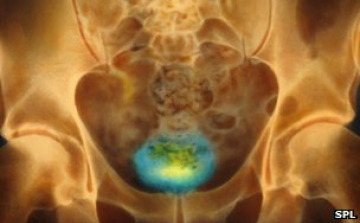

Gerinssérülteknek segíthet a hólyag irányításában egy új készülék

Brit kutatók kifejlesztettek egy készüléket, amely gerincsérülteknek segíthet a hólyag irányításában.